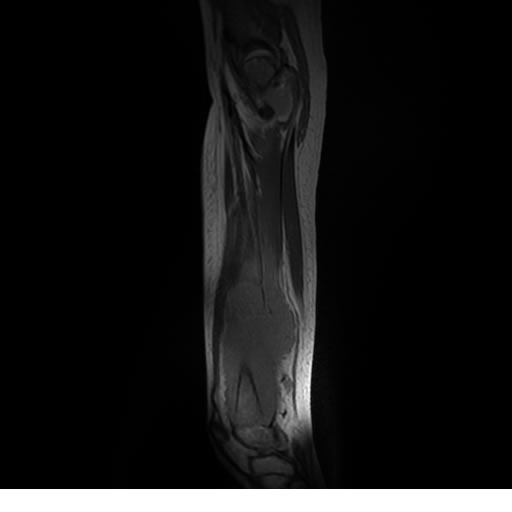

Se realiza estudio de MRI de muslo izquierdo en diferentes planos, con secuencias de Spin Echo, GRE; ponderadas a T1 y a T2, se utilizan pulsos de saturación de grasa y se administra medio de contraste IV a base de Gadolinio en base al peso del paciente.

La diáfisis femoral izquierda muestra reacción perióstica importante, se extiende desde el cuello del fémur, invade trocánteres, diáfisis femoral, medial y distal, es compatible con un proceso infeccioso óseo, el complejo muscular del muslo se ve edematizado.

Desde el punto de vista patológico, el tumor suele localizarse en la diáfisis de huesos largos (como fémur, tibia o húmero), pero también puede afectar costillas, pelvis y columna vertebral. A medida que la lesión progresa, se produce destrucción ósea, formación de tejido blando tumoral y reacción perióstica característica.

La resonancia es la modalidad de elección para valorar la extensión intramedular y la infiltración en tejidos blandos, brindando una imagen más detallada del compromiso tumoral. Los hallazgos característicos incluyen:

Lesión de señal heterogénea en secuencias T1 (hipointensa) y T2/STIR (hiperintensa), que refleja necrosis, hemorragia y contenido celular diverso.

Realce intenso y heterogéneo tras la administración de contraste (gadolino), lo que indica vascularización tumoral.

Compromiso de la médula ósea adyacente y de estructuras vecinas, como músculos y neurovasculatura.

Posible presencia de edema óseo y necrosis central.